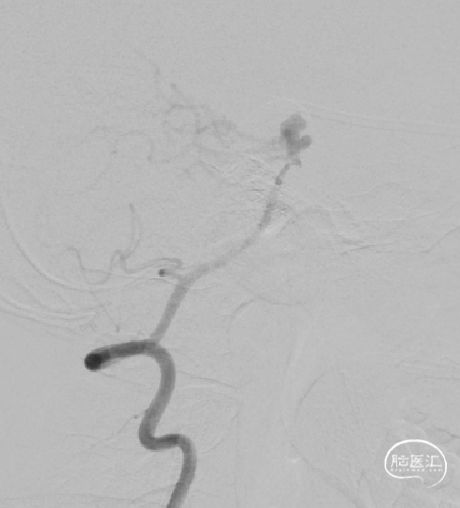

DSA:右侧P1段一6.8*9.7mm不规则囊状突起动脉瘤,远端P2段呈螺旋状蛇形动脉瘤改变。

DSA:右侧P1段一6.8*9.7mm不规则囊状突起动脉瘤,右侧A1段动脉瘤。夹层蛇形动脉瘤。

DSA:评估右侧后交通。

右侧颈内正位

术后即刻复查:远端血管通畅、支架打开良好。

术后正位复查